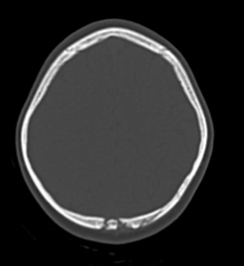

CT protocol + Pathology?

• C- brain

• Depressed skull fracture: parts of the skull have sunken into the cranium.

• There is steps within the cortical margins of the frontal and temporal bones